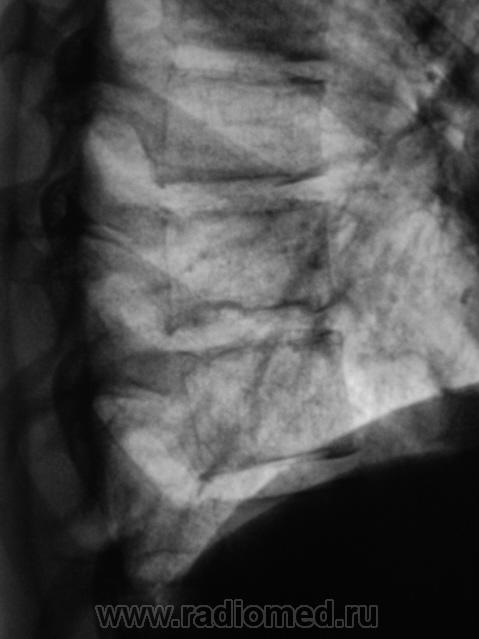

В заключительной части протокола рентгенологического исследования высказано мнение о наличии правосторонней среднедолевой (крупозной) пневмонии. Описаны изменения в грудном позвонке (фрагмент боковой рентгенограммы).

Ну а что на счет  тела позвонка.Какая-то спондилопатия?

По всей видимости, грыжи Шморля, но это - "по всей видимости".

В протоколе исследования грыжа Шморля, как таковая, не фигурировала. По поводу "позвоночника", мы патологию указываем достоверно только после проведения линейной томографии, именно позвоночника, которая в данном случае не проводилась.